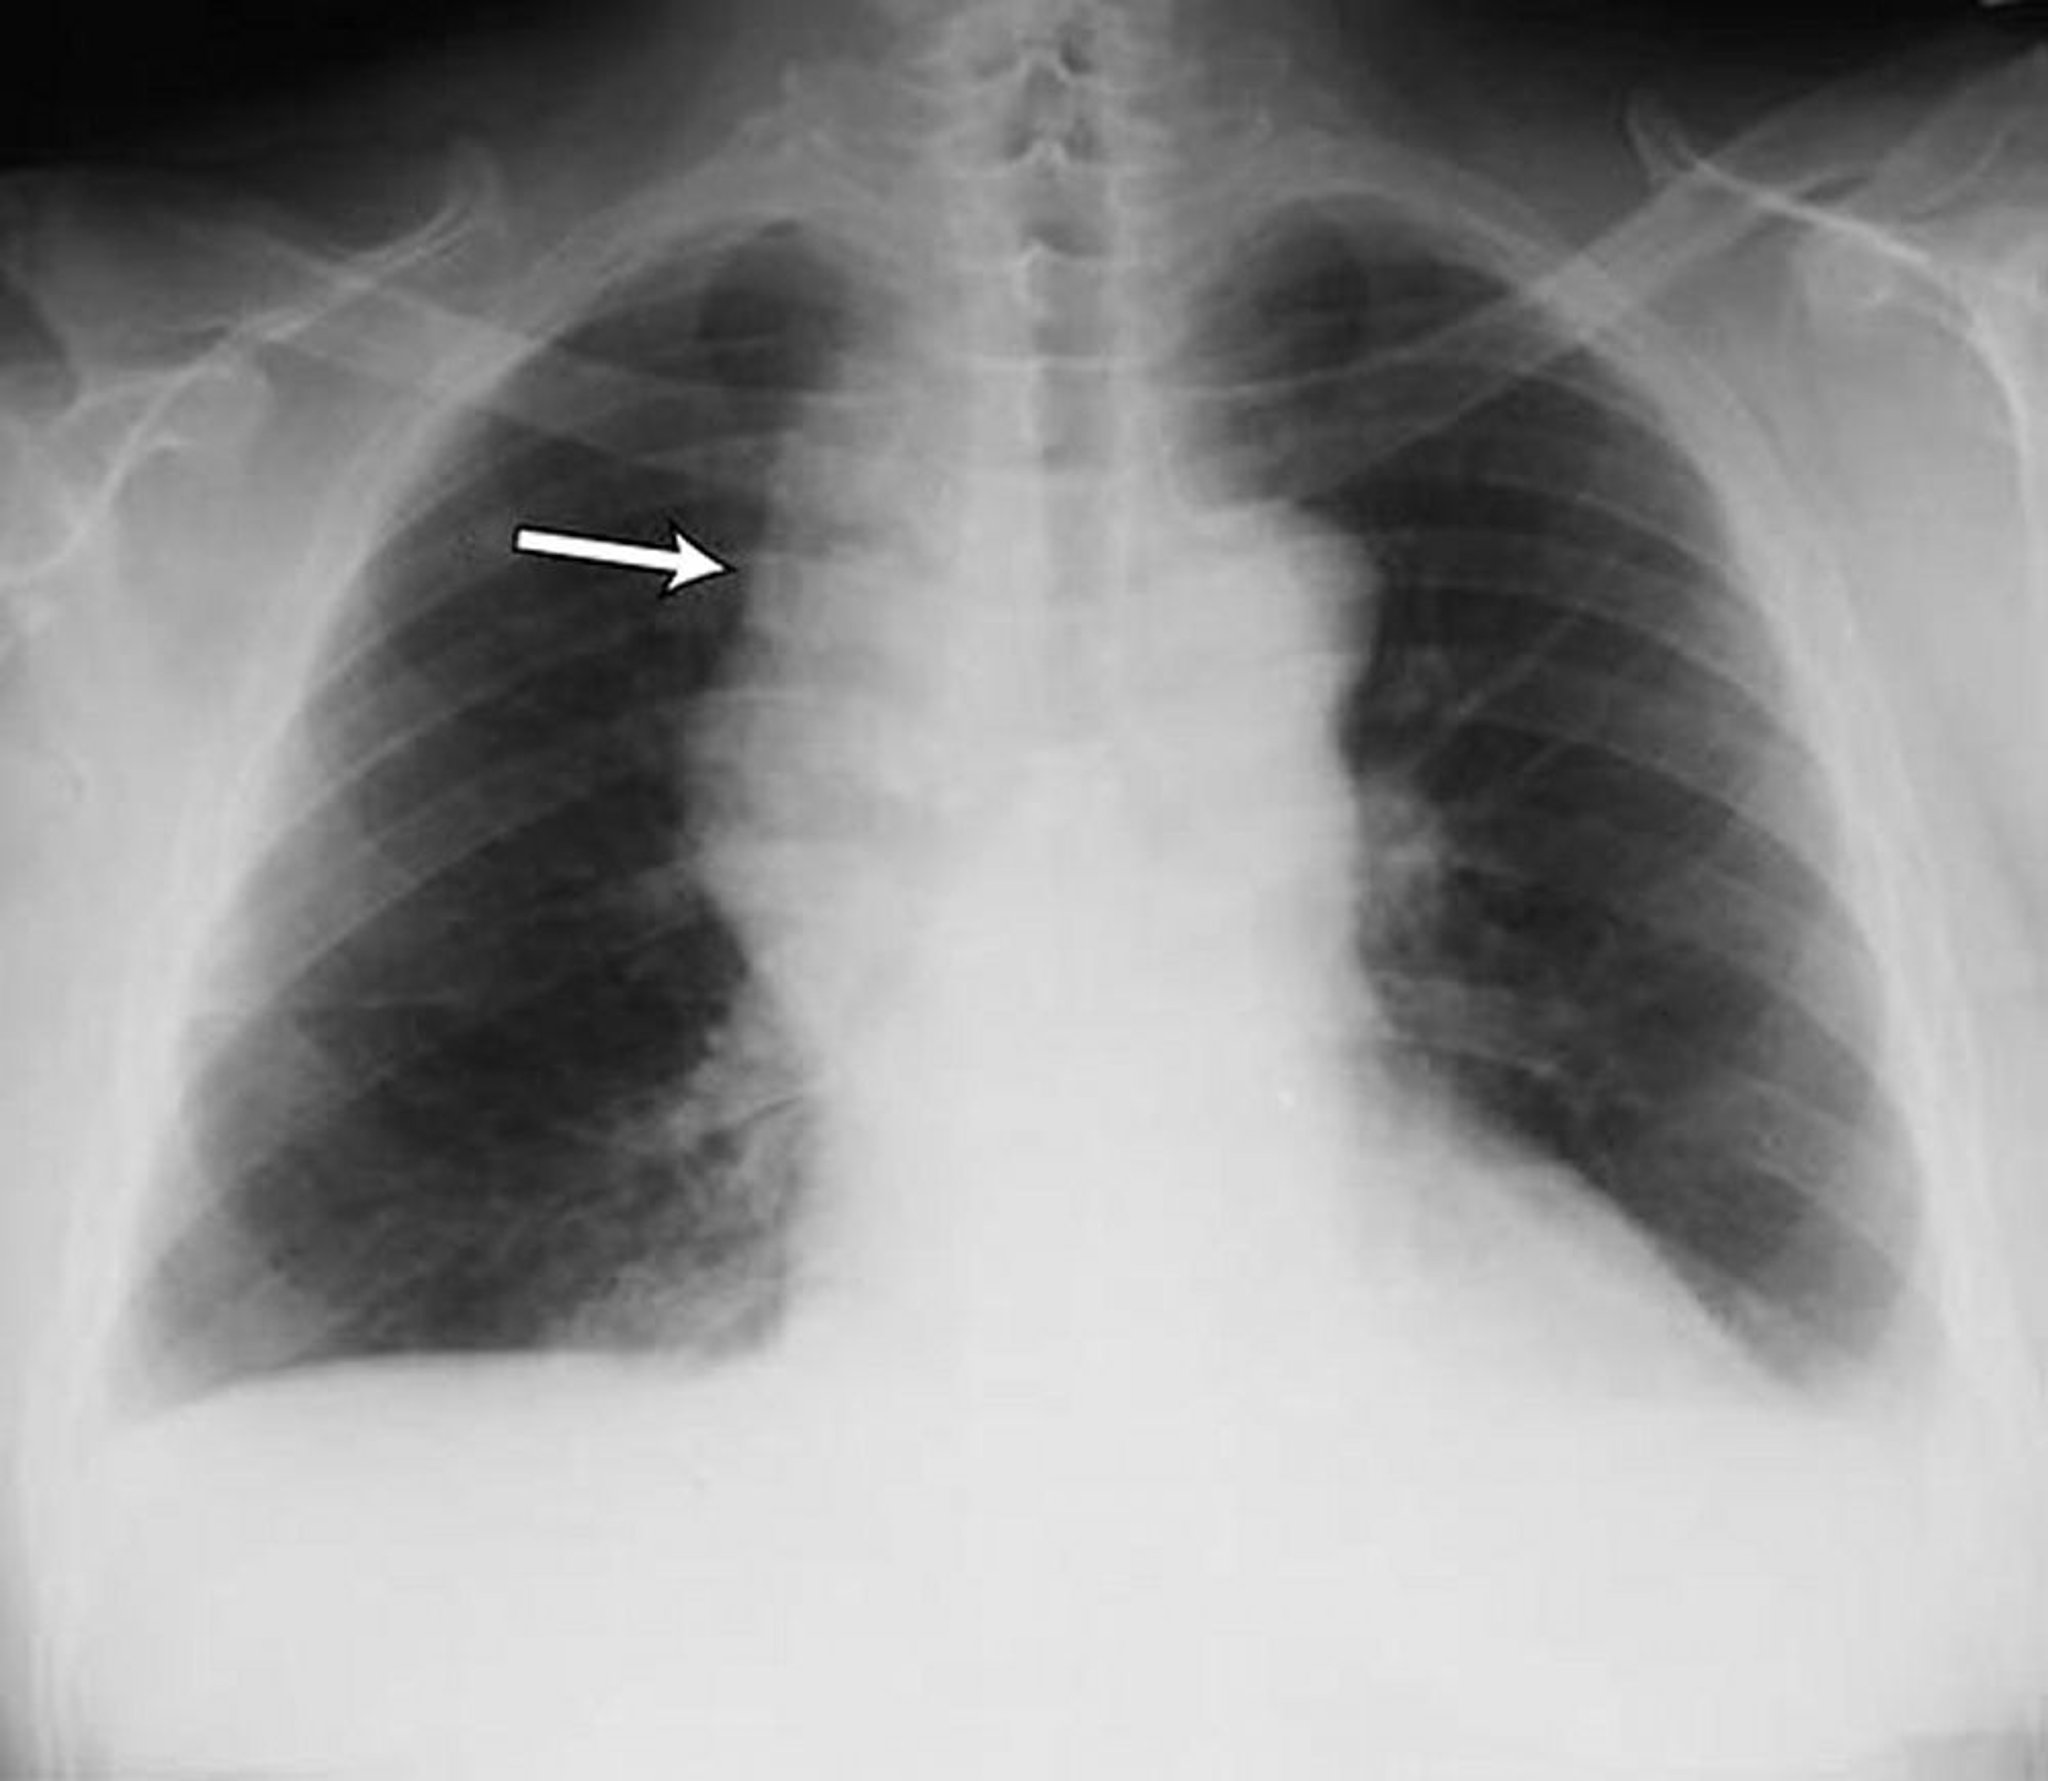

Esta foto mostra aumento dos linfonodos cervicais em um paciente com linfoma não Hodgkin. Ambos os ângulos costofrênicos opacificados. A seta indica o alargamento do mediastino alargado pelo linfoma.

By permission of the publisher. From Huggins J, Sahn S. In Bone's Atlas of Pulmonary and Critical Care Medicine. Edited by J Crapo. Philadelphia, Current Medicine, 2005.